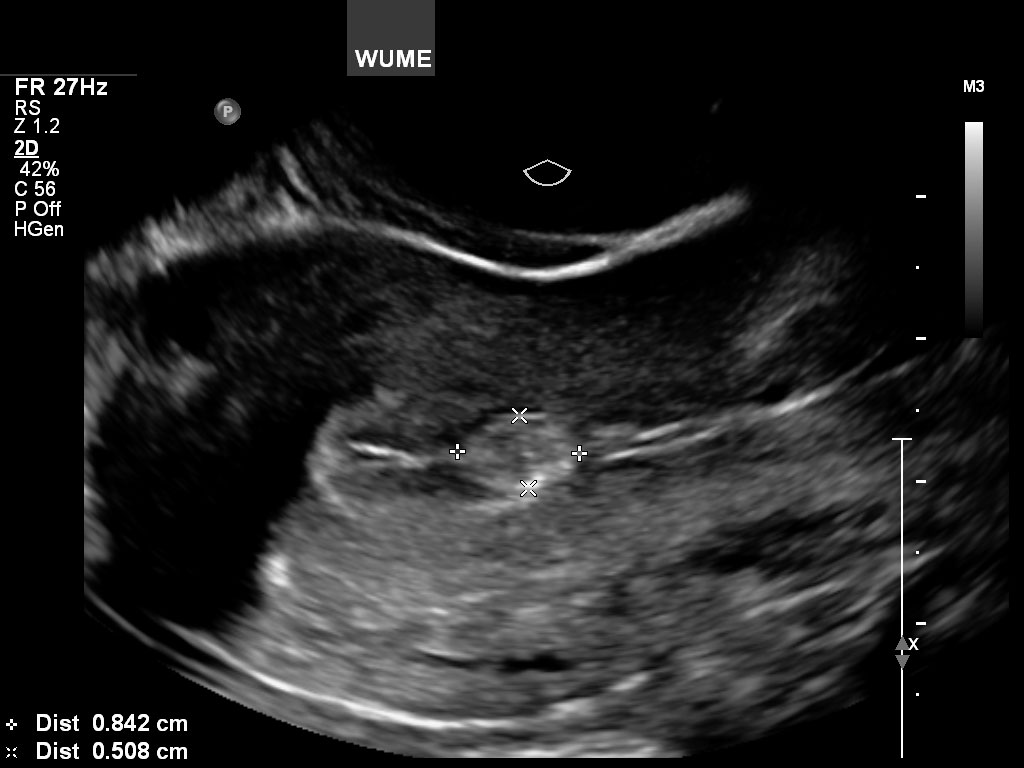

پولیپ آندومتر

پولیپهای آندومتر معمولاً در طول سالهای قاعدگی ایجاد میشوند و معمولاً باعث پریودهای سنگین و خونریزی بین دورهها میشوند. آنها در لایه داخلی رحم یا آندومتر یافت می شوند که بافتی است که هر ماه با پریود خونریزی می کند. آنها معمولاً خوش خیم هستند و به راحتی توسط متخصص زنان برداشته می شوند.